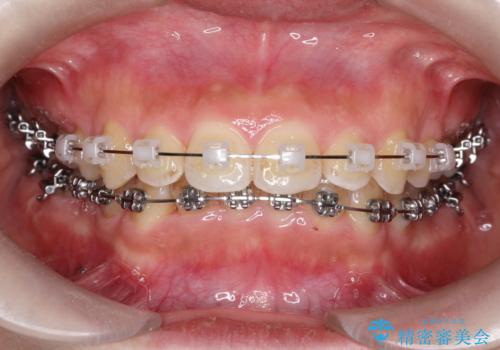

- 矯正装置

- ワイヤー装置

治療中、装置の変更を希望されたため上下で装置が異なっています。